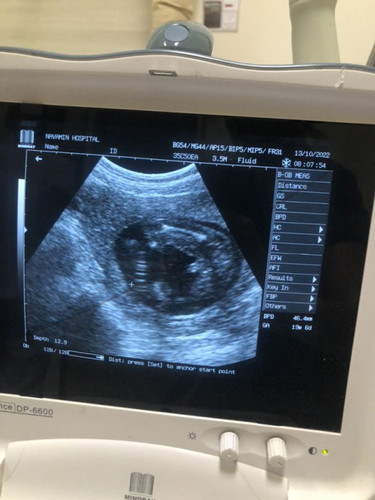

19 week น้ำหนักเด็กในท้อง5ขีด

อยากถามแม่ๆน้ำหนักน้องอยู่ในเกณฑ์ใช่มั้ยคะ น้ำหนักแม่ขึ้นมา6กิโลค่ะ ได้ลูกชาย😅

ตอนเราซาว 19w หนักเกิบ3ขีดเอง 289 กรัมหมอบอกตามเกณฑ์ ส่วนแม่น้ำหนักขึ้นมา2โล ถามหมอว่าขึ้นเยอะไปไหมค่ะ หมอบอกไม่ค่ะ กำลังพอดี

บ้านนี้ตอน 18wอัลตราซาวด์ น้องน้ำหนัก271 หมอบอกน้ำหนักตามเกณฑ์นะคะ ส่วนแม่ขึ้นมา 2กก.จ้า